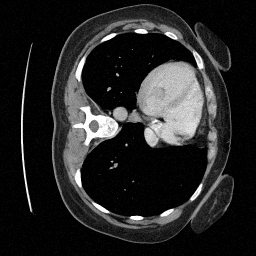

Training an NCSN on Abdomen CT - I

Figure 2: Some example images from the validation split.